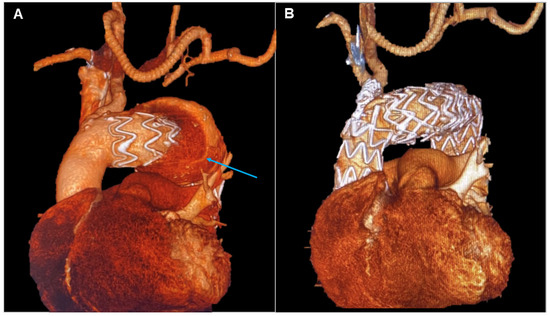

Figure 1.

Patient 1’s Computed Tomography Angiography showing a Penetrating Aortic Ulcer (PAU) of the aortic arch (A) and the complete exclusion of the PAU after Thoracic Endovascular Aortic Repair (TEVAR) with reduction in the dimension of the pseudoaneurysm (B).

Following a period of clinical observation without further episodes of chest pain, a customized cone-shaped prosthesis was designed to accommodate the proximal aortic arch dilatation. It featured a scalloped design to fit the origin of the left carotid artery and included a fenestration for the left subclavian artery (Terumo, Custom Relay Plus 38-32 × 180 mm). A stent was placed at the origin of the left subclavian artery and inserted through the fenestration to ensure branch patency. Additionally, to ensure proper prosthesis adaptation and prevent potential type I endoleak formation, endovascular ballooning with transvenous rapid cardiac pacing was performed to seal the proximal end of the aortic prosthesis in Ishimaru Zone 1 (Figure 1).